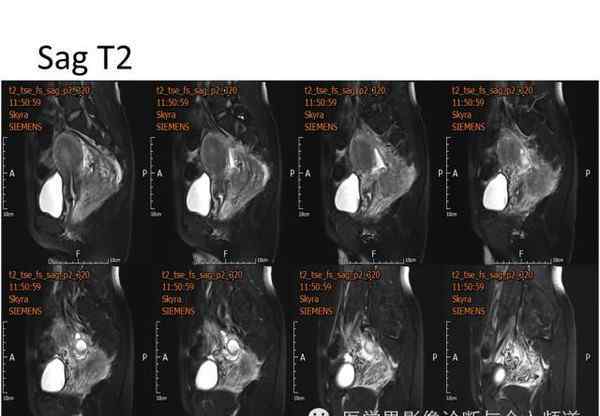

核磁共振平片扫描和增强扫描显示:

盆腔内可见弥漫性长T1长T2异常信号,FS-T2WI可见高信号,涉及直肠左前壁、直肠侧韧带和宫颈等。边界不清,盆腔可见条带状FS-T2WI高信号强度。注射钆喷酸葡胺后,病情明显加重。